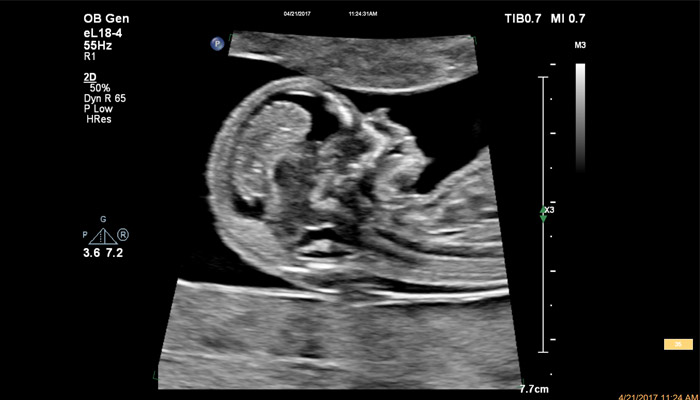

Начало новой жизни - это всегда особое время! Ультразвуковые решения Philips в области акушерства разработаны для того, чтобы позволить врачам сосредоточиться на здоровье каждой будущей мамы. Разработанные для обеспечения клиницистов дополнительной информацией ультразвуковые решения Philips позволяют получать не только детальную визуализацию анатомии плода уже в первом триместре, но и помогают оптимизировать рабочий процесс врача. Применение eL18-4 в I триместре беременности Сегодня ультразвуковая диагностика используется для выявления генетических аномалий, внутриутробных пороков, оценки жизнеспособности плода и определения срока беременности, как наиболее эффективный метод. Ультразвуковое исследование плода в первом триместре (до 13 недель 6 дней беременности включительно) является наиболее точным методом. В течение многих десятилетий трансвагинальный метод ультразвукового исследования был «золотым стандартом» диагностики в акушерстве. Сегодня линейный матричный датчик может стать альтернативой общепринятому трансвагинальному методу оценки состояния плода и репродуктивных органов женщины. Детальная анатомия плода и ранняя диагностика пороков в I триместре Ультразвуковое исследование является основным методом визуализации для оценки врожденных аномалий плода. Линейный матричный датчик eL18-4 позволяет получить детальную информацию об анатомии плода и выявить пороки на ранней стадии развития. Сверхширокополосная PureWave матрица датчика генерирует частоты в диапазоне 2-22 МГц, что формирует одинаково высокоинформативные, четкие изображения по всей глубине сканирования до 14 см.

Высокочастотный датчик Philips eL18-4 содержит решетку из 1920 активных монокристаллических пьезоэлементов, выполненных по усовершенствованной технологии PureWave. Это обеспечивает высокодетальную 2D визуализацию, которая в совокупности с глубиной сканирования необходима для уверенной диагностики в акушерстве.

До введения высокочастотных линейных датчиков точная ультразвуковая диагностика мочевой системы плода была доступна в основном после 16-17 недель беременности. Новая технология еL18-4 позволяет проводить раннюю морфологическую оценку плода уже в первом триместре. Клинический случай с применением eL18-4 демонстрирует, что кортико-медуллярная дифференцировка почек плода возможна на 14 неделе беременности”.

Использование линейного матричного датчика eL18-4 при осмотре беременных в I триместре, особенно на ранних сроках, позволяет ограничиться трансабдоминальным сканированием вместо трансвагинального и при этом получить максимально полную диагностическую информацию. Отсутствие полостного исследования чрезвычайно важно для соблюдения принципа ALARA – использования минимальной необходимой мощности для безопасности пациента. Благодаря применению мультичастотного датчика с диапазоном от 2 до 22 МГц через переднюю брюшную стенку хорошо определяется эмбрион длиной 3 мм, что соответствует шестой неделе беременности. В конце I триместра с eL18-4 достаточно отчётливо визуализируется четырёхкамерный срез сердца, мочевой пузырь и сосуды пуповины, которые, как правило, определяются только при трансвагинальном сканировании.

Во II триместре беременности высокая разрешающая способность eL18-4 позволяет детально изучить структуру органов и тканей и увидеть многие нюансы, которые при работе другими датчиками не обнаруживались или становились очевидны в более поздние сроки. Например, у 19-недельного плода визуализируется перегородка носа, мышцы языка, диафрагма между грудной и брюшной полостью, на 20-й неделе чётко определяются оболочки спинного мозга и уретра, а на 24-й – хорошо дифференцируются корень лёгкого, борозды и извилины мозжечка и многие другие структуры.